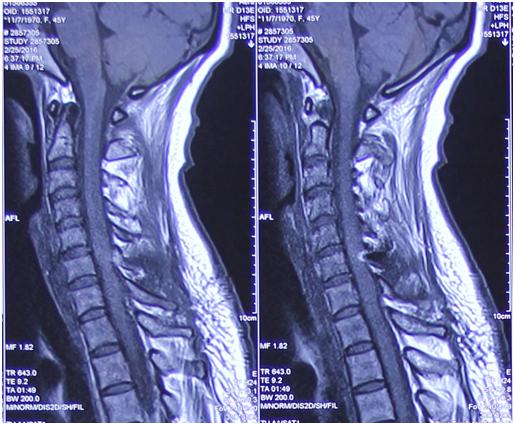

影像学资料:

手术前后对比:

术中,主刀者李维新教授仔细操作,避免脊髓神经损伤,全切肿瘤。术后患者症状缓解明显,无明显不适。

李维新教授介绍,此例手术的难度在于肿瘤完全位于脊髓的腹侧,手术中需要对脊髓进行轻度的翻转,从脊髓的侧方进入腹侧把肿瘤完全切除,肿瘤切除在显微镜下有一定的难度,但是并不是特别复杂。而且,由于患者为良性肿瘤,粘连不是太紧,把他这个粘连的这个载瘤神经分离出来肿瘤是可以完全切除,作为这种良性肿瘤来说完全切除了就是治愈了,而且完全切除了之后就不会再复发了。